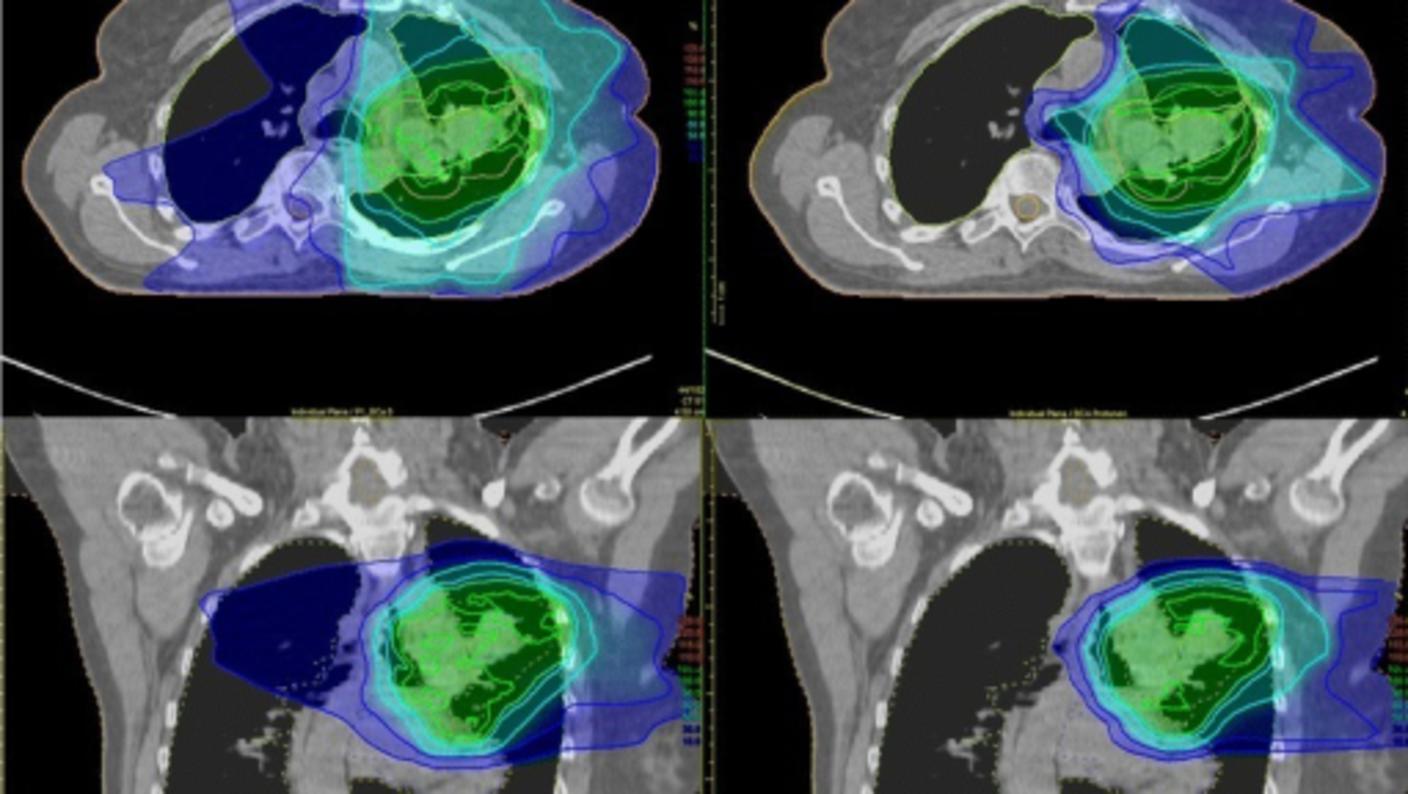

Protons are particles with a positive charge. Like photon beams, proton beams can also reach tumors deep in the body. However, proton beams do not scatter radiation on their path through the body and they stop once they reach the tumor. Doctors think that proton beams might reduce the amount of normal tissue that is exposed to radiation. Clinical trials are underway to compare radiation therapy using proton beams with that using photons beams. Some cancer centers are using proton beams in radiation therapy, but the high cost and size of the machines are limiting their use.

There are many types of external beam radiation therapy, all of which share the goal of delivering the highest prescribed dose of radiation to the tumor while sparing the normal tissue around it. Each type relies on a computer to analyze images of the tumor in order to calculate the most precise dose and treatment path possible.

3-D conformal radiation therapy is a common type of external beam radiation therapy. It uses images from CT, MRI, and PET scans to precisely plan the treatment area, a process called simulation. A computer program is used to analyze the images and to design radiation beams that conform to the shape of the tumor.

3-D conformal radiation conforms to the shape of the tumor by delivering beams from many directions. The precise shaping makes it possible to use higher doses of radiation to the tumor while sparing normal tissue.